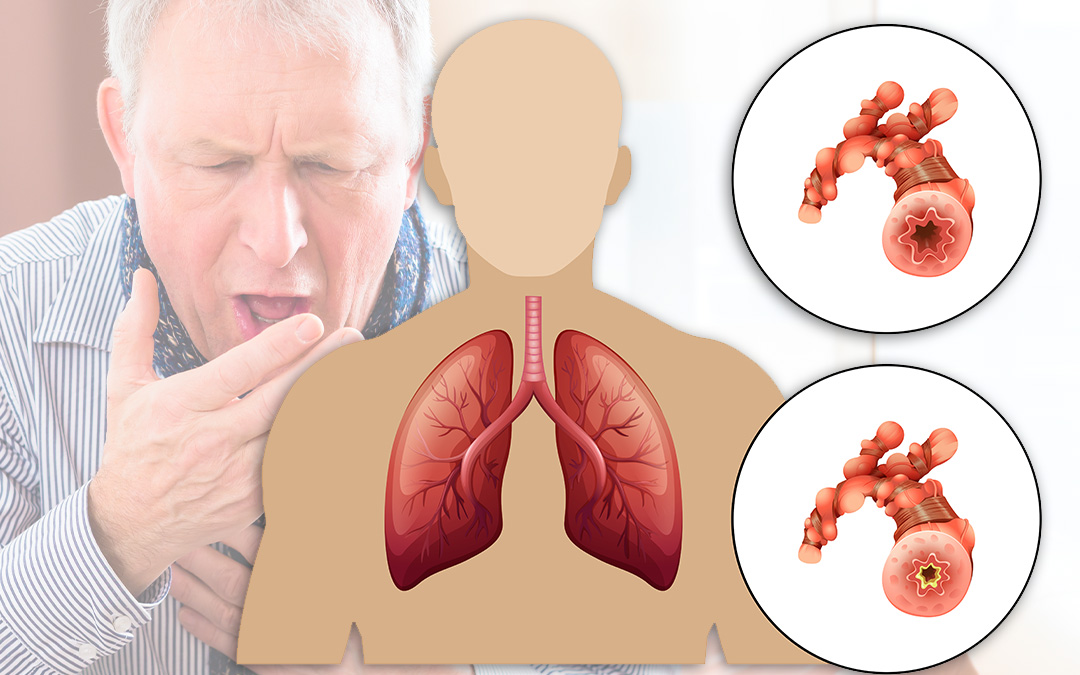

ფქოდ-ის დროს კვებას ძალიან დიდი მნიშვნელობა ენიჭება. ფილტვების ქრონიკული ობსტრუქციული დაავადება სასუნთქი გზების დაავადებათა ჯგუფს მოიცავს, მათ შორის: ემფიზემას და ქრონიკული ბრონქიტს.

უფრო ზუსტად, ფქოდ არის სასუნთქი გზების სანათურის პერსისტული ანუ მუდმივად არსებული ობსტრუქცია, რომელიც მხოლოდ ნაწილობრივ შეიძლება იყოს შექცევადი და საინჰალაციო ტოქსინების, უფრო ხშირად კი თამბაქოს კვამლის ზემოქმედების შედეგად აღმოცენებული ანთებითი რეაქციის შედეგია.

მედიკამენტოზურ მკურნალობასთან ერთად, ფილტვებისთვის განკუთვნილი დიეტა სუნთქვას აუმჯობესებს, სიმპტომებს ამსუბუქებს და სასუნთქ სისტემასაც აძლიერებს.